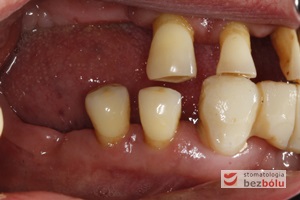

Braki zębowe w strefach bocznych szczęki i żuchwy - widoczne starcie patologiczne na skutek przeciążeń okluzyjnych w odcinku przednim

Braki zębowe w strefach bocznych szczęki i żuchwy – widoczne starcie patologiczne na skutek przeciążeń okluzyjnych w odcinku przednim